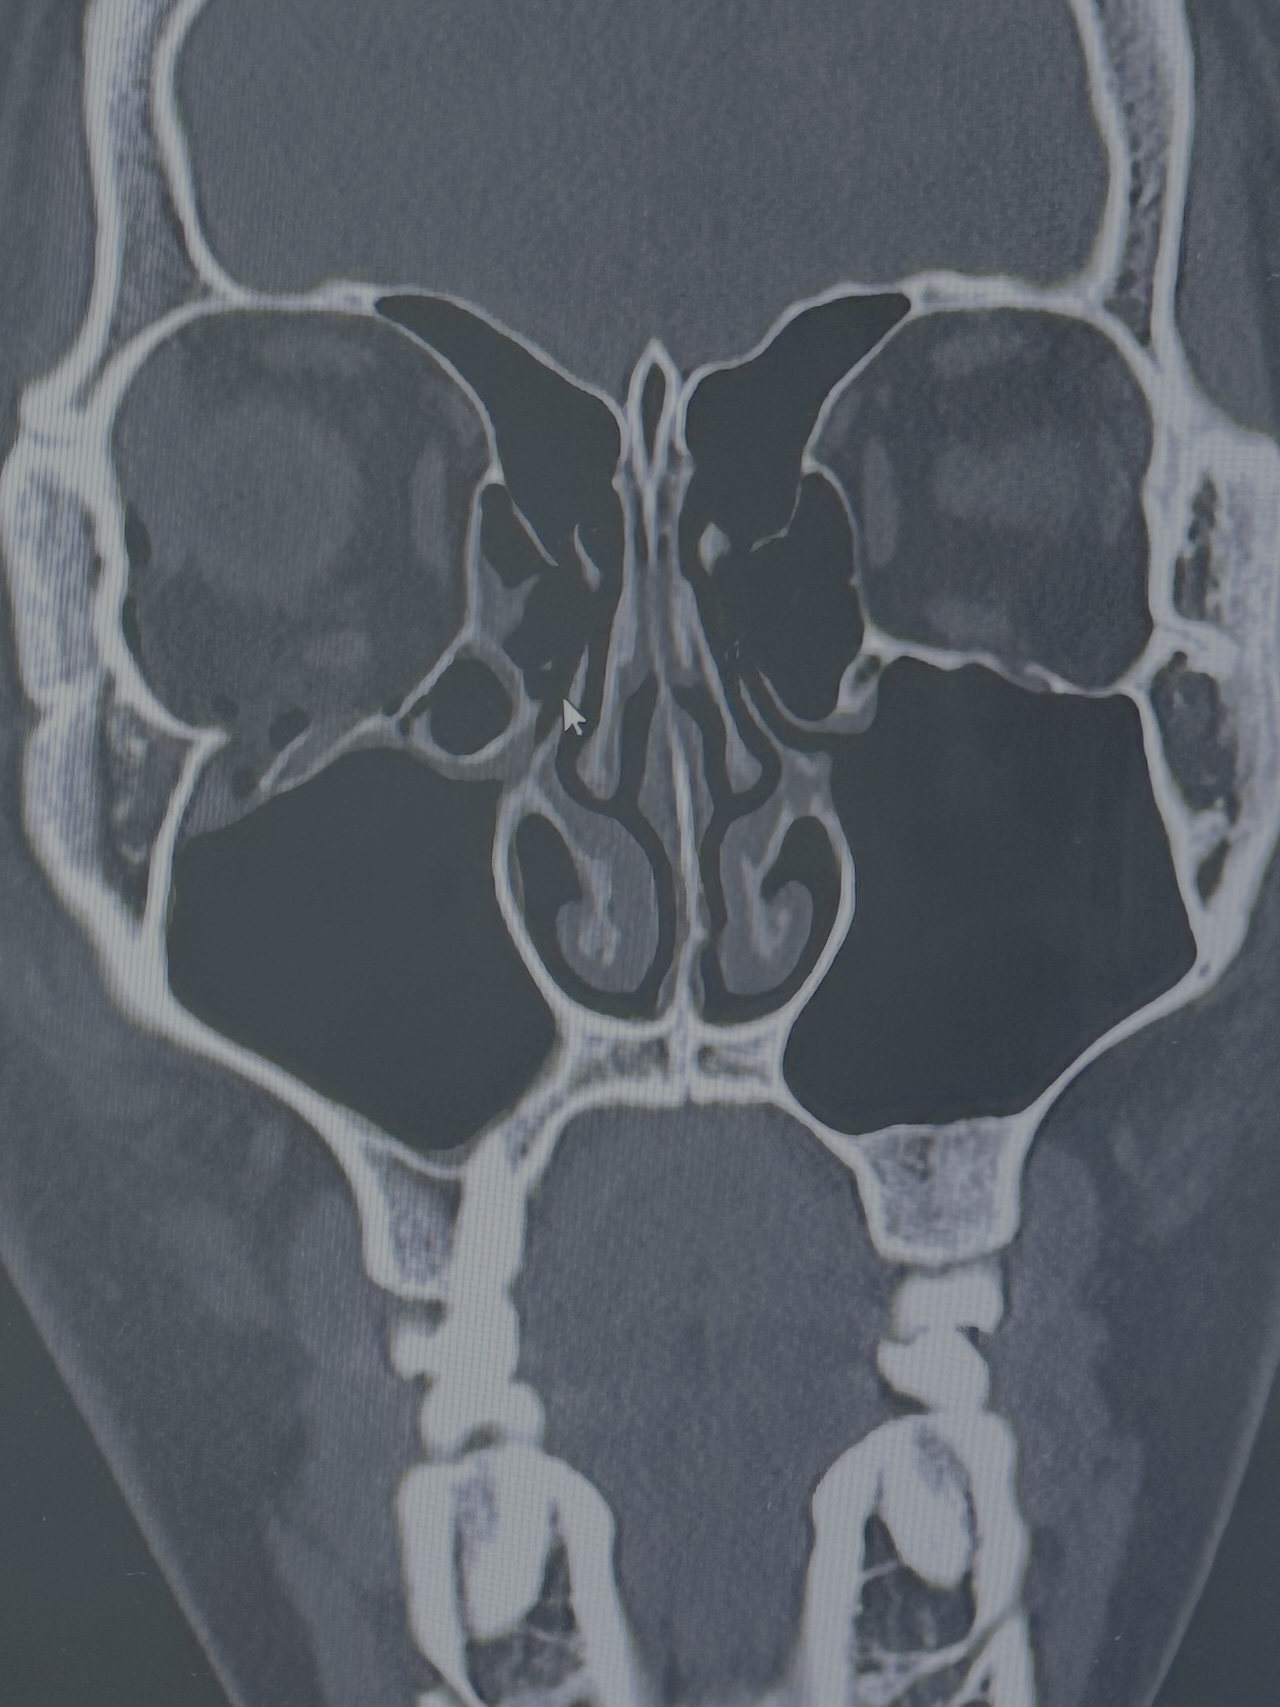

약 4일 전 폭행 피해로 인해 안와골절을 당했습니다.

다만 진료를 받아보니 수술에 관해서 굉장히 애매하다고 하시며 골절이 일어난 부위의 크기는 수술을 할만한데 기능적인 문제는 없다보니 수술을 하게된다면 안구함몰 예방 수술이 될거라고 하십니다.

차라리 수술 전에 안구함몰 증상이 일어난다면 확실하게 결정할 수 있을 듯 한데 정말 모르겠습니다. 원장님은 해당 CT를 바탕으로 안구함몰이 발생할 확률이 어느정도라고 생각하시나요?

마지막으로 해당 CT사진을 봤을 때 원장님꼐서는 수술여부에 대해 어떻게 생각하시나요?

일단 교과서에 나와 있는 수술적응에는 해당합니다. 하벽 50% 이상의 면적이 골절되거나 골절된 뼈가 5mm 이상 어긋나 있을 경우 수술을 하는 게 좋다고 되어 있는데요, 언뜻 봐도 골절면은 절반이 되지 않아도 골절로 밀린 하벽이 5mm 이상은 되어 보이네요.

수술은 2주 이내에 하면 되는데요, 3주를 넘기지는 말라고 되어 있습니다.

당장 결정은 하지 않으셔도 2주까지 기다려 보시다가 안구함몰이 조금이라도 생기는 것 같으면 수술을 생각하시면 될 것 같습니다.